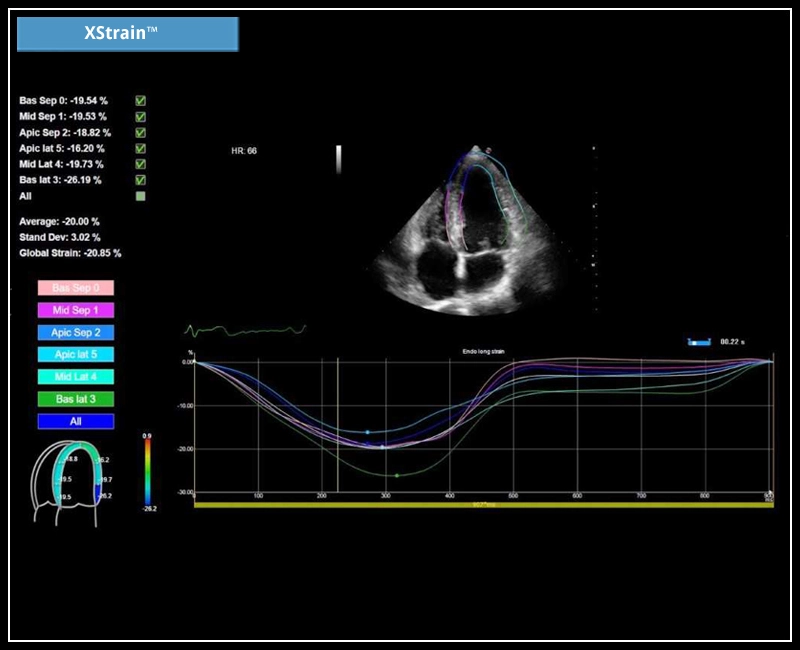

MyLab™X7 - XStrain

MyLab™X7 - XStrain